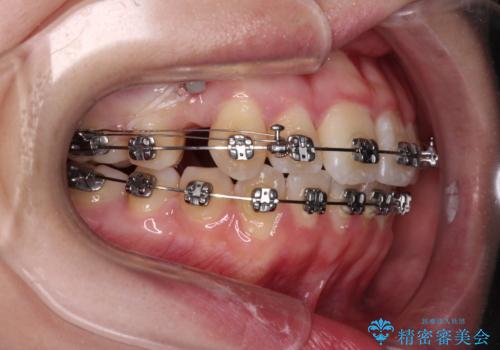

【モニター】八重歯を片側の抜歯矯正で治す メタルブラケット装置

- 八重歯とずれた正中を気にして来院された患者様です。

非抜歯矯正ではデコボコを解消することでより口元が突出する可能性があるため、上顎右右側の小臼歯1本の抜歯を行い、ワイヤー装置による矯正治療を行うこととしました。

正中位置を合わせるために、上顎臼歯部にアンカースクリューを埋入することとしました。